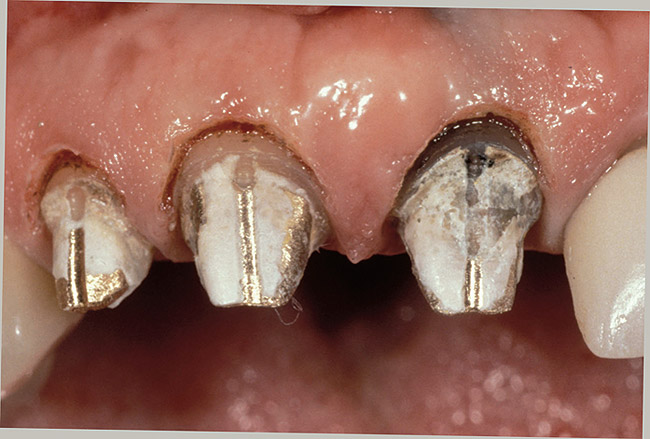

Figure 1  View of 4 porcelain veneer preparations with the margins placed at the level of tissue.

Figure 1

Figure 2  Note the invisibility of the marginal line in the completed veneers, even though the margin has not been carried below tissue.

Figure 2

A clinician is faced with 3 options for for margin placement when considering an anterior esthetic restoration: supragingival, equigingival (ie, even with tissue), and subgingival.1 The supragingival or equigingival margin will have the least impact on the periodontium and, classically, was only used in nonesthetic areas because of the stark contrast in color and opacity of traditional restorative materials. With the advent of adhesive dentistry, resin cements, and more translucent restorative materials, the ability to place supragingival or equigingival margins even in esthetic areas is now a reality (Figure 1 and Figure 2). The primary requirement of a material to enable its use in esthetic areas supra- or equigingivally is a high level of cervical translucence. Materials such as feldspathic porcelain, as well as pressable ceramics, meet this requirement. Consequently, whenever possible, these restorations should be chosen not just for their esthetic advantages, but for their favorable periodontal impact as well. The greatest biologic risk occurs when placing subgingival margins.2